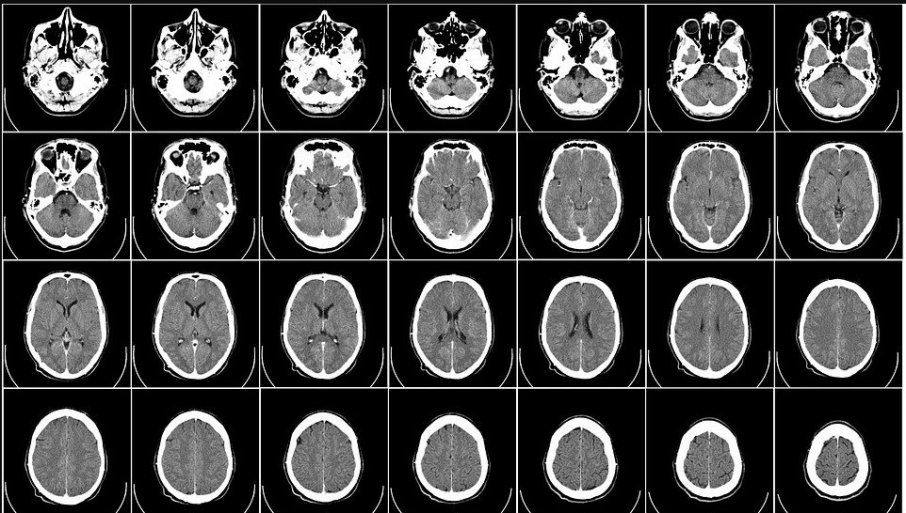

Tretman se vrši tako što pacijent prima ciljane električne impulse, a veliki broj istraživanja pokazuje dobre rezultate tog lečenja.

Elektrode su povezane žicom sa uređajem postavljenim ispod kože u grudima pacijenta koji kontroliše količinu električne stimulacije i isporučuje konstantne niskonaponske impulse.

Lekari kažu da stimulacija pomaže jer neuroni komuniciraju pomoću električnih i hemijskih signala.

U normalnom mozgu, električna aktivnost neometano odjekuje u svim oblastima. Čini se da DBS "odlepljuje kolo", dozvoljavajući mozgu da radi ono što bi inače radio.

Neka kasnija istraživanja su pokazala da pacijenti sa depresijom osećaju stabilno, dugoročno olakšanje nakon terapije sa DBS. Ali neki lekari su skeptični, ukazujući na potencijalne komplikacije kao što su krvarenje, moždani udar ili infekcija nakon operacije.